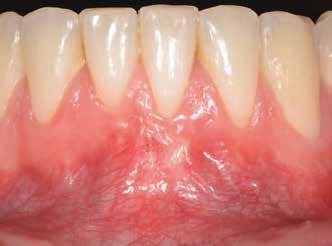

1. ábra: Műtét előtti fogászati panorámafelvétel, amelyen a hiányzó felső állcsont jobb első premolárisát és a szabad véggel rendelkező hidat láthatjuk. — 2. ábra: Az implantátum méreteinek megtervezése CBCT-vel. 3. ábra: Bukkális lágyrészdefektus. — 4. ábra: A biológiai szélesség értékelése a vertikális lágyszövetvastagság alapján. 5. ábra: Palatinális „tekercslebeny” – Palatal roll flap. — 6. ábra: Bredent medical copaSKY 4x10 implantátumbeültetés. 7. ábra: Szubkresztális implantátumbeültetés a várható biológiai szélességnek megfelelően.

8. ábra: Egyéni ínyformázó titánbázison, tulipán alakú emergenciaprofillal. — 9. a. ábra: A sebzárás okkluzális nézete.

bukkális nézete.

(2. ábra). A lágyszövetek értékelése Seibert szerinti I. osztályú csontdefektust állapított meg (3. ábra), ezért a beavatkozáskor palatinális „tekercslebenyt” preparáltunk (palatal roll flap), és implantációt végeztünk, hogy kompenzálni tudjuk a bukkális lágyszövet-behúzódást. Megmértük a vertikális lágyszövetvastagságot, és úgy terveztük, hogy a szubkresztális implantátum beültetése összhangban legyen a biológiai szélesség kialakulásával a transzgingivális gyógyulási periódus alatt (4. ábra)